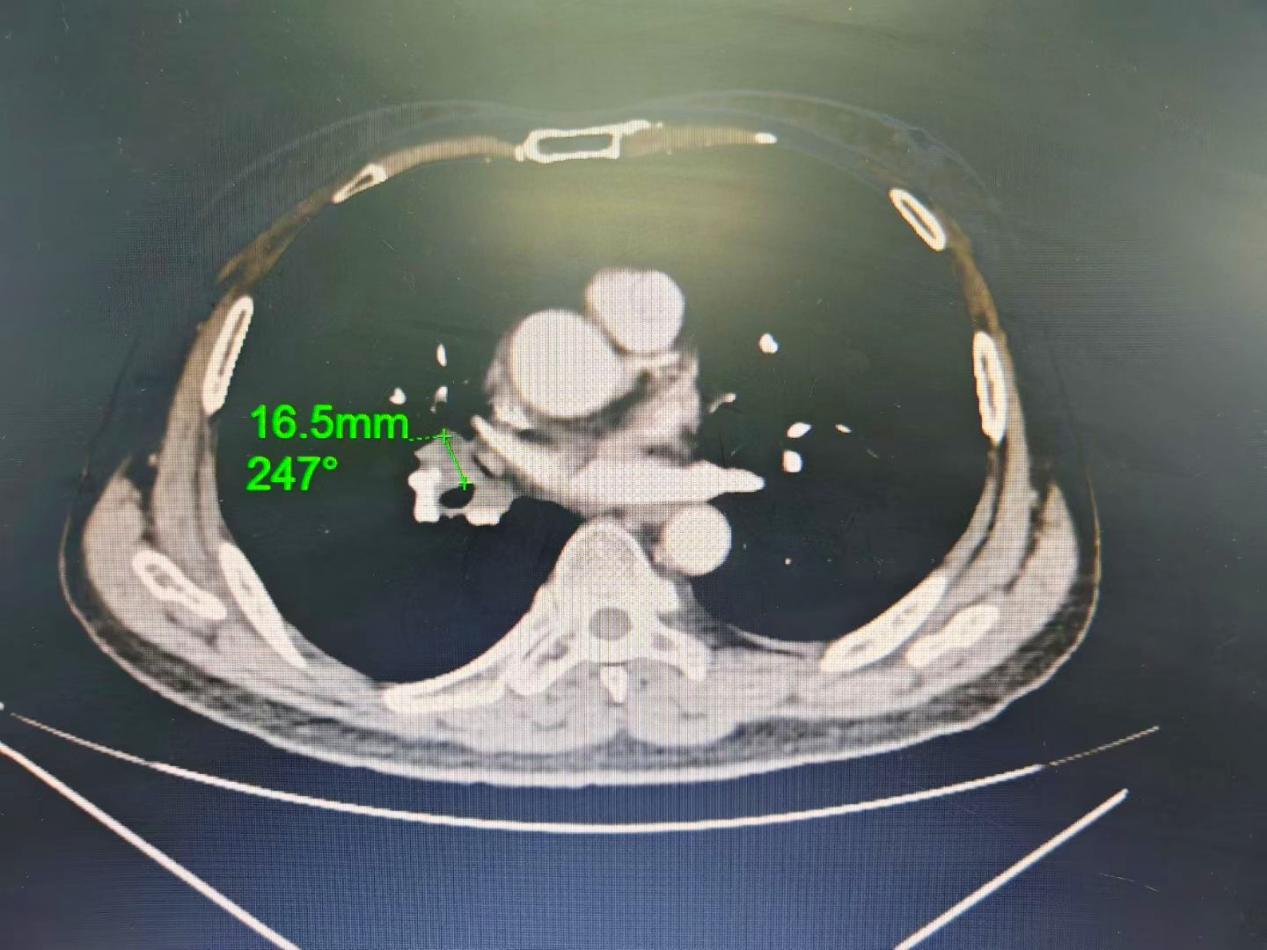

此次接受手术的患者为61岁男性,确诊肺癌后一直在玉林市红十字会医院呼吸与危重症医学科一、二病区接受规范抗肿瘤治疗,病情控制平稳。近期复查胸部CT时,提示其右肺淋巴结异常肿大,结合病史,临床高度怀疑肿瘤出现进展。

术前胸部CT定位